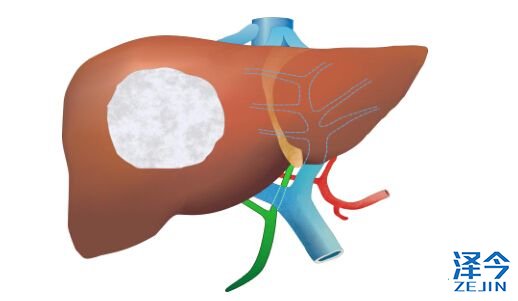

瑞戈非尼:肝癌治疗空白被填充

上海泽今医疗了解到:瑞戈非尼刚在美国获批允许应用于肝癌的治疗,还未过一年,瑞戈非尼针对于肝癌的治疗在中国也获得批准,这体现了瑞戈非尼本身的优秀以及瑞戈非尼受到医学界的高度认可,今天,上海泽今医疗就带您了解一下瑞戈非尼。

上海泽今医疗先带您追溯一下上一个针对于肝癌的靶向药物,索拉非尼多吉美。大家能想起索拉非尼是什么时候获批治疗肝癌的吗?应该是已经有近十年的时间了,也就是说近十年的时间里,肝癌是没有新药可以应用的。

对于瑞戈非尼肝癌适应症在华批准,中国科学院院士、复旦大学附属中山医院院长、上海市肝病研究所所长樊嘉教授介绍:分子靶向治疗是晚期肝癌在手术、介入等局部治疗手段之外的全身治疗重要进展,索拉非尼在过去十年帮助很多中国肝癌病人延长了生存时间。对于索拉非尼治疗进展的病人,拜耳创新药物瑞戈非尼的获批是近十年来的重要突破,瑞戈非尼的上市将造福更多的中国肝癌病人。

国家肝癌专家组组长、中国临床肿瘤学会肝癌专委会主委、解放军南京八一医院全军肿瘤中心秦叔逵教授也说到:分子靶向药物索拉非尼一线治疗可以明显延长中晚期肝癌患者的生存期,已成为目前肝癌的标准治疗。但部分患者用药后仍会发生疾病进展,急需二线治疗药物。瑞戈非尼作为更新换代的靶向新药,在欧美已获批肝癌二线治疗适应症,本次在中国经 CFDA快速优先批准,可以解决该类患者人群迫切的治疗需求,值得在临床上推广应用。这也是中国肝癌治疗向全程管理新时代迈进的一个里程碑事件。可喜可贺!